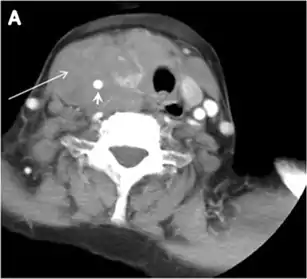

Thyroid nodules that are detected by an imaging study but have not been previously detected or suspected clinically are considered to be ITNs. ITNs are one of the most common incidental findings on neck imaging. ITNs are reported in up to 25% of chest CT scans, and in 16–18 % of cervical region cross-sectional imaging, including CT and MRI scans. The rate of malignancy in the detected ITNs on CT and MRI scans varies from 0% to 11%. Incidentally detected thyroid carcinomas are more likely to be papillary thyroid carcinomas (PTCs) (Fig. 3). Incidentally detected cancers tend to be smaller in size and less likely to have distant metastasis, as compared to clinically suspected thyroid cancers.[1]

On CT scans, a malignant lesion is suspected when the margins are ill-defined and there is extra-thyroid extension, lymph node involvement, or invasion of the surrounding structures. The absence of these features does not exclude malignant tumours, especially papillary, follicular, and medullary thyroid carcinomas (Fig. 3). Therefore, ultrasound is the modality of choice for thyroid lesion evaluation, due to its superior spatial resolution compared to CT examinations. Sonographic features of malignancy are micro-calcifications, acoustic shadowing, anti-parallel orientation, marked hypoechogenicity, irregular or microlobulated margins, and increased vascularity. CT scans lack the ability to detect these reliable sonographic signs of malignancy. Therefore, further management of ITNs, if required, usually begins with thyroid ultrasound and FNA should be considered according to the ultrasound findings.[1]